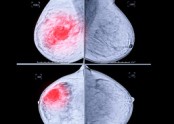

- ▶ 정기 검진중 미세 석회화가 발견되었다고 합니다.

- ■ 정기적으로 유방촬영하는 것이 왜 중요할까요? ① 아래 환자분은 30대 중반에 검진상 양성 석회화가 있던 분으로 5년 되던 40세에 국가암 검진을 했고, 이때 과거에는 보이지 않던 소견으로 유방촬영 하부 작은 부위에 …